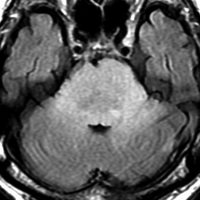

MRI画像所見 60代で嚥下障害と構音障害で発症した例

延髄から中脳まで腫瘍があって脳幹部が腫れています。この画像ですと,小児のびまん性橋膠腫(DIPG,びまん性正中グリオーマ)のように見えます

両側視床から大脳基底核,両側大脳半球深部白質,脳梁まで広範囲に腫瘍が存在します。退形成性星細胞腫のようにまだらにガドリニウム増強されます。